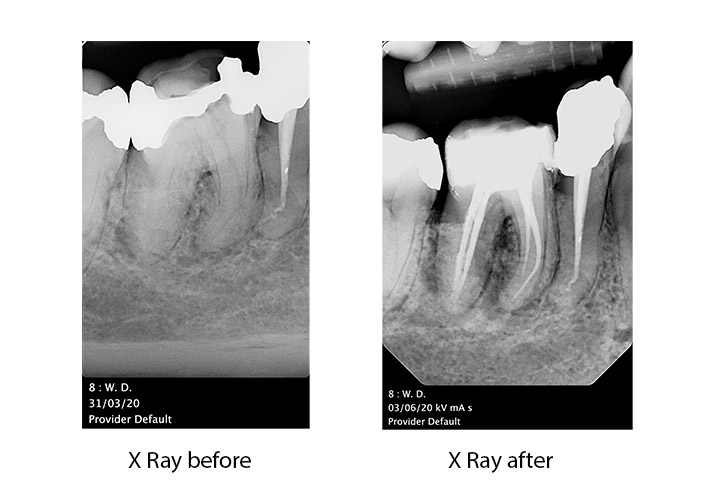

Endodontics is a speciality of dentistry that is concerned with the prevention, diagnosis and treatment of disease or injury to the dental pulp. The pulp, which some people call “the nerve,” is the soft tissue inside the tooth that contains the nerves and blood vessels and is responsible for tooth formation. Root canal treatment is a safe and effective means of saving teeth that may otherwise be lost.